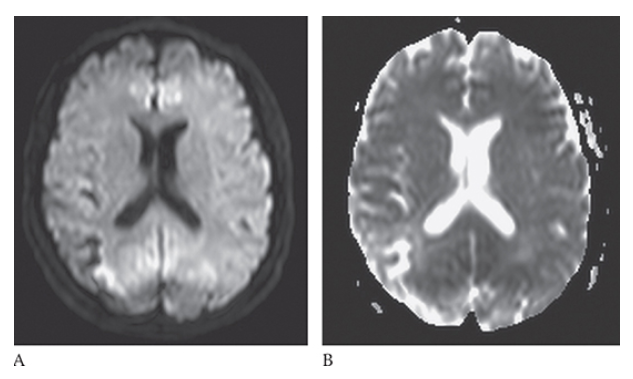

What is A

Ischemic Stroke. In an acute stroke the diffusion will be bright and the ADC map will be dark

What is B

Ischemic Stroke. In an acute stroke the diffusion will be bright